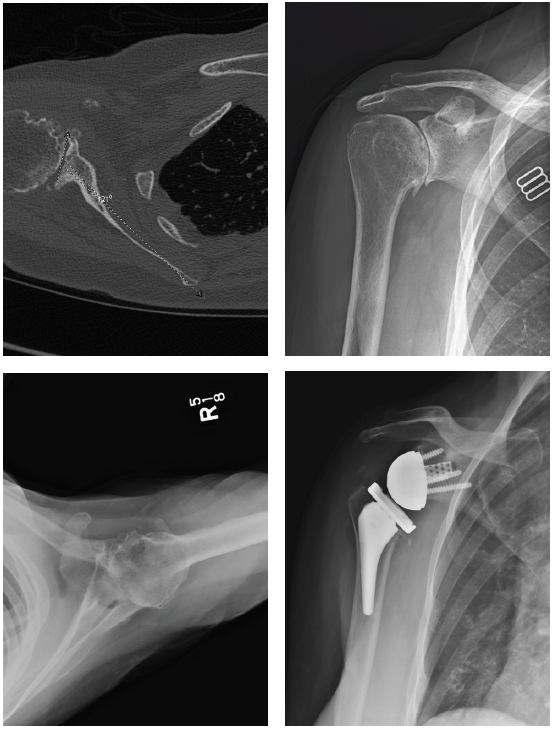

Patient 1: Primary anatomic total shoulder arthroplasty using Equinoxe Preserve short stem and caged glenoid.

- Active male in his 60s, retired reporter with surprisingly good preop motion

- This patient is a good candidate for either a stemless anatomic or a short stem anatomic

- Six (6) weeks postop his external rotation (ER) has returned to preop baseline of 45 degrees, and his forward flexion (FF) has improved from 90 to 145 degrees.